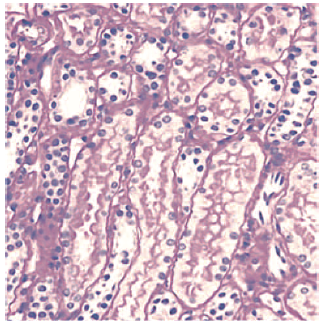

A 42-year-old white male was referred with chronic LPHS following renal stones

some years earlier. At time of assessment, no stones, hydronephrosis, or

ureteric abnormalities were seen on computed tomography scan. Donor 2 had normal

blood tests, and renal biopsy showed no organic cause for the pain (Figure 2).

Laparoscopic denervation had previously been performed and had provided

temporary benefit; however, the pain had returned in the absence of an organic

cause.

The patient was unable to control pain despite opiates and neuropathic analgesia; medical history also noted that the patient had taken methadone regularly and had a history of drug addiction. Despite full assessment from the pain team and escalation of treatment and support for his addiction, the pain became a persistent issue. He was offered autotransplant but refused and opted for a native nephrectomy, following a full medical and psychiatric assessment. The MAG3 renogram showed a 50:50 split, and baseline creatinine level was 68 IU/L. Laparoscopic removal of the organ was uneventful, and he was symptom free within 7 days postsurgery. His 1-year eGFR was 69 mL/min/1.73 m2, baseline creatinine was 89 IU/L, urea level was 6.1 mg/dL, and hemoglobin level was 139 g/L. He also no longer required treatment for drug addiction.

Loin pain hematuria syndrome is a rare and somewhat controversial disease and remains a diagnosis of exclusion, with an estimated prevalence of 0.012%. It was first reported in 1967 in 3 female patients with recurrent attacks of severe flank pain and intermittent macroscopic hematuria. Demographic data on cases are limited, but it is thought to predominantly affect young, white women, who also are one of the highest donating groups with regard to organ donation.18,19 The most prominent clinical features include periods of severe or intermittent loin pain accompanied by either microscopic or gross hematuria, which can present unilaterally or bilaterally.19 It is believed that microvascular abnormalities may be the underlying cause of LPHS, stimulating hypersensitivity and spasm. However, renal biopsies from patients with LPHS rarely reveal significant pathology, suggesting a strong psychosomatic component, and thus the syndrome preserves renal function.18

Figure 2. Loin Pain Hematuria Syndrome Normal Biopsy Result From Donor 2